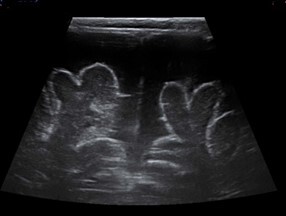

Neonatology Wide Subarachnoid Space 3 Image